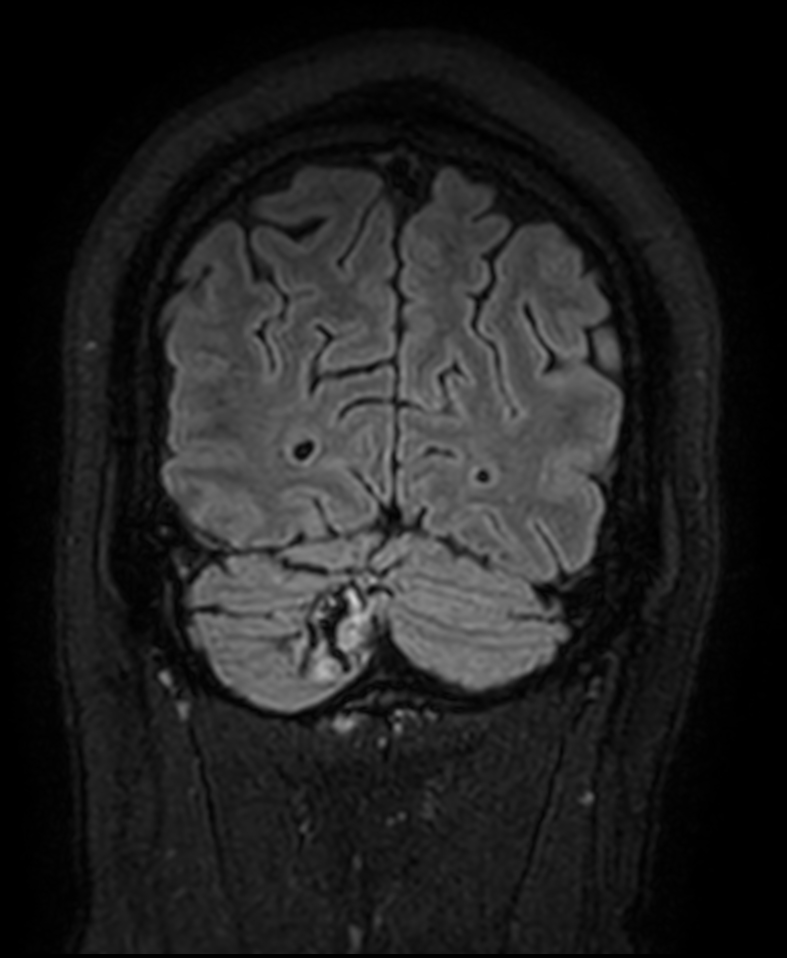

Patient with a lesion in the cerebellum. The ExamCard includes Compressed SENSE to accelerate the entire exam and techniques for motion reduced imaging (MultiVane XD), 3D imaging to acquire high resolution data in multiple directions, 3D susceptibility weighted imaging (SWIp), angiography sequences (Time-of-Flight and Contrast-Enhanced MRA with both arterial and venous phases), DTI with MultiBand SENSE to acquire a high number of diffusion directions in a short scan time and EPIC Brain to bring down any residual distortion.

T2w FLAIR Compressed SENSE